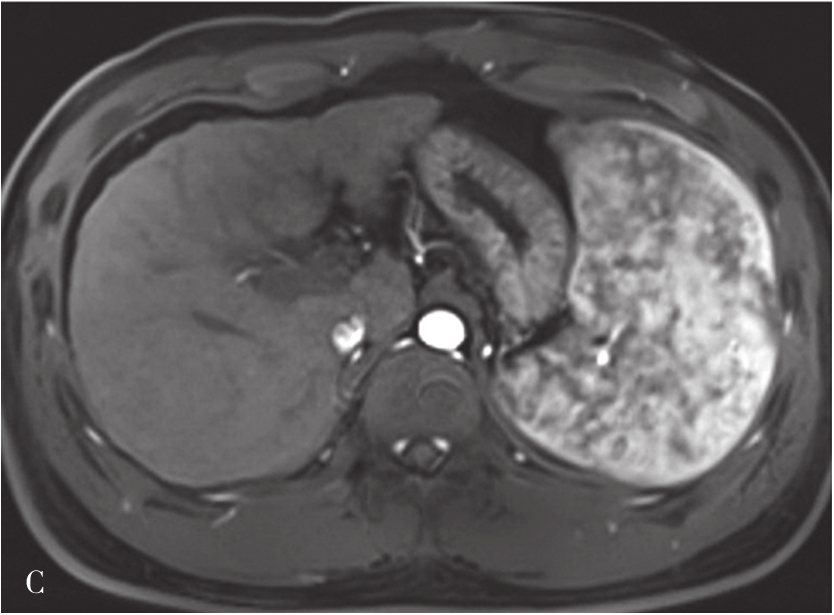

3)超声造影表现:

HCC绝大多数为肝动脉供血,门静脉供血减少,超声造影表现为造影剂微泡动脉期快速进入肿瘤微血管内,使肿瘤快速增强,增强模式与增强CT/MRI检查类似,典型HCC超声造影表现为快进-快退,即动脉期高增强,门静脉期与实质期由于门静脉血供减少,并且由于病灶内缺乏Kupffer细胞或Kupffer细胞功能不全,不能摄取造影剂,而呈低增强。HCC非典型超声造影表现主要在两方面:首先表现为动脉期增强模式,肿瘤超声造影达高峰时非均匀性增强或环形增强;其次表现为增强时相上表现为慢进-慢出,即肿瘤开始增强时间晚,与肝实质同步,或消退时间晚,门静脉相及延迟相未减退。非典型增强模式多为分化较好的HCC,因其以门静脉供血为主,使得诊断困难,需要穿刺进行组织学进一步判断。肝细胞癌超声造影动脉期、静脉期及延迟期声像图表现如图5-21-18~图5-21-20所示。

图5-21-18 原发性肝细胞癌超声造影动脉期呈高增强

图5-21-19 原发性肝细胞癌超声造影静脉期呈低增强

图5-21-20 原发性肝细胞癌超声造影延迟期呈低增强